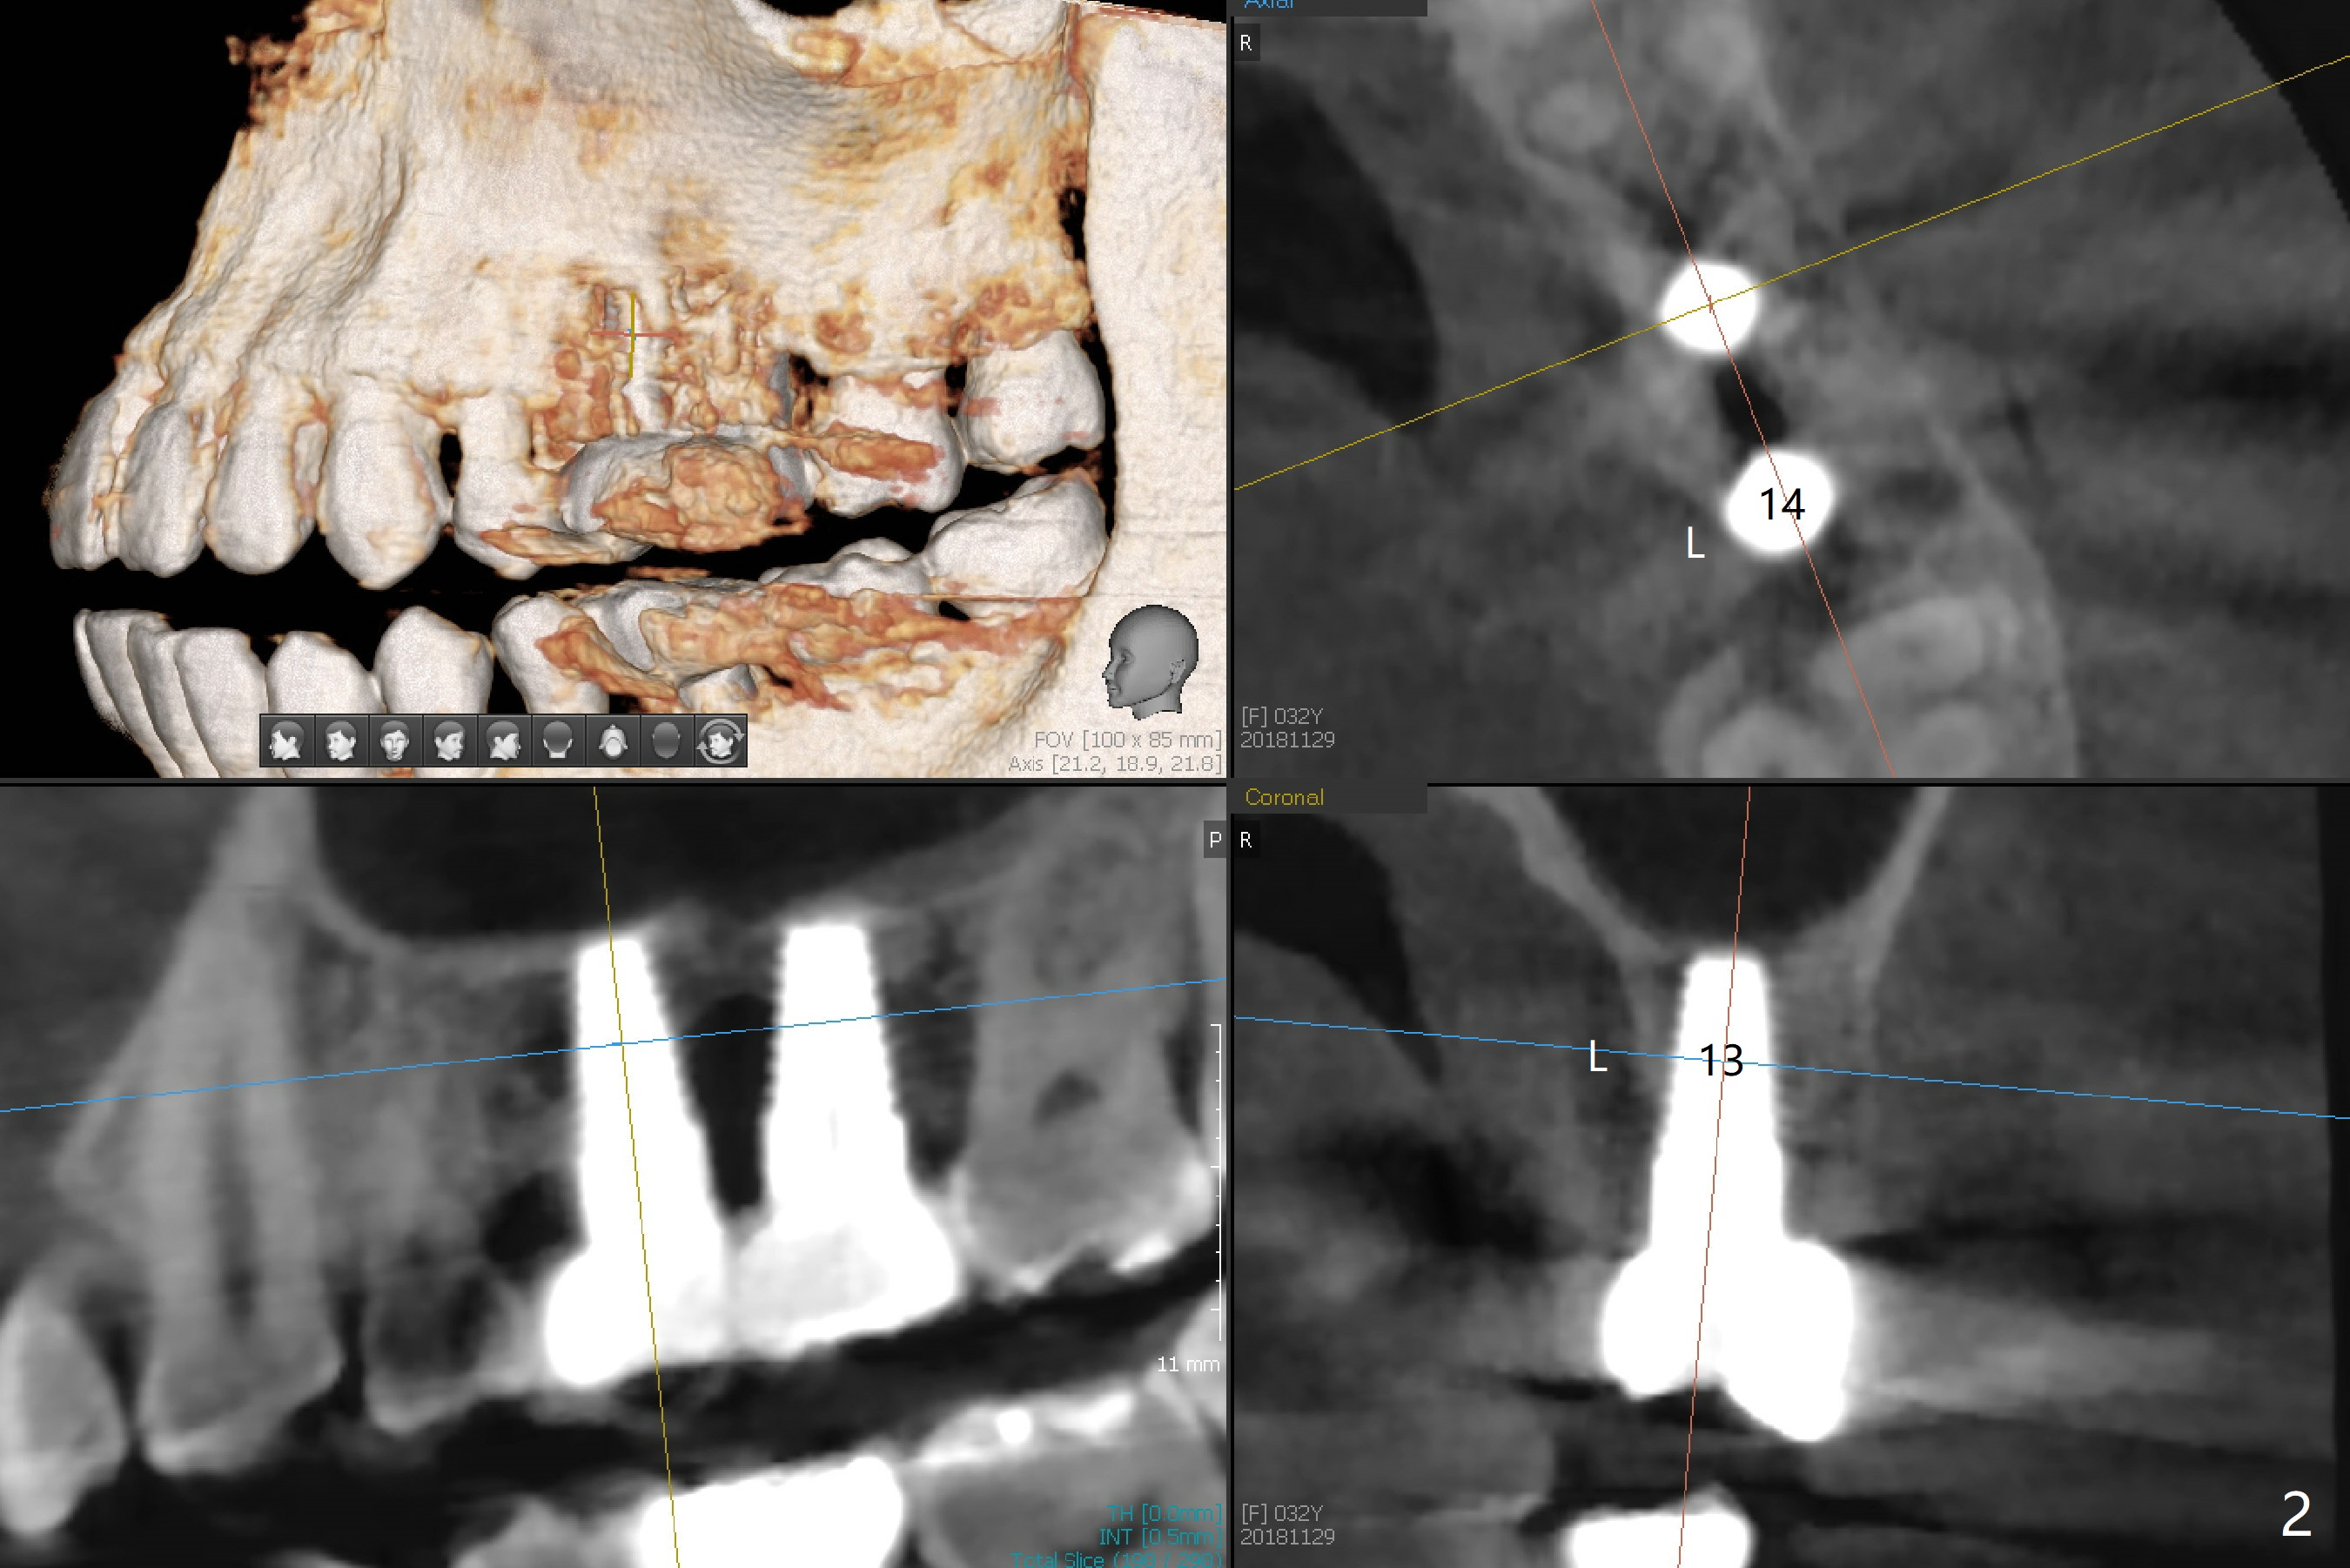

A 32-year-old woman develops periimplantitis (severe hemorrhage and deep pockets) at #14 three years 7 months post cementation (Fig.1).  A 4.5x11 mm implant is placed with flap at #13 after failure for the 1st time (Fig.2), while a 5x11 mm implant is placed flapless with sinus membrane perforation.  Uniposts are cemented with Ketac.  The lingual plate at #14 is defective (Fig.3).  The implant at #14 will be removed flapless, followed by Osteogen plug (most likely sinus floor defect) and bone graft.  After healing, an implant will be placed with guide.  By breaking the proximal contacts, the crown, abutment and implant at #14 are shaken loose using forceps.  Finally the crown breaks off.  Make a slot on the top of the abutment and use a screw bit to turn the abutment/implant counterclockwise.  There is abundant granulation tissue with arterial hemorrhage associated with granulation tissue removal.  The defect involves the distal surface of the implant at #13 and the mesial surface of the tooth #15.  Therefore bone graft is deposited in these surfaces (Fig.4 arrowheads, as compared to preop BW, Fig.4').  The periodontal dressing seems to remain in place asymptomatic 7 days postop (Fig.5).  The bone height 5.5 months postop should be enough for implantation (Fig.6).  To avoid marker associated with guided surgery, free hand will be adopted.  Sinus lift with PRF is expected.  To place in the middle of the ridge buccopalatally, incision will be made with bone expansion.